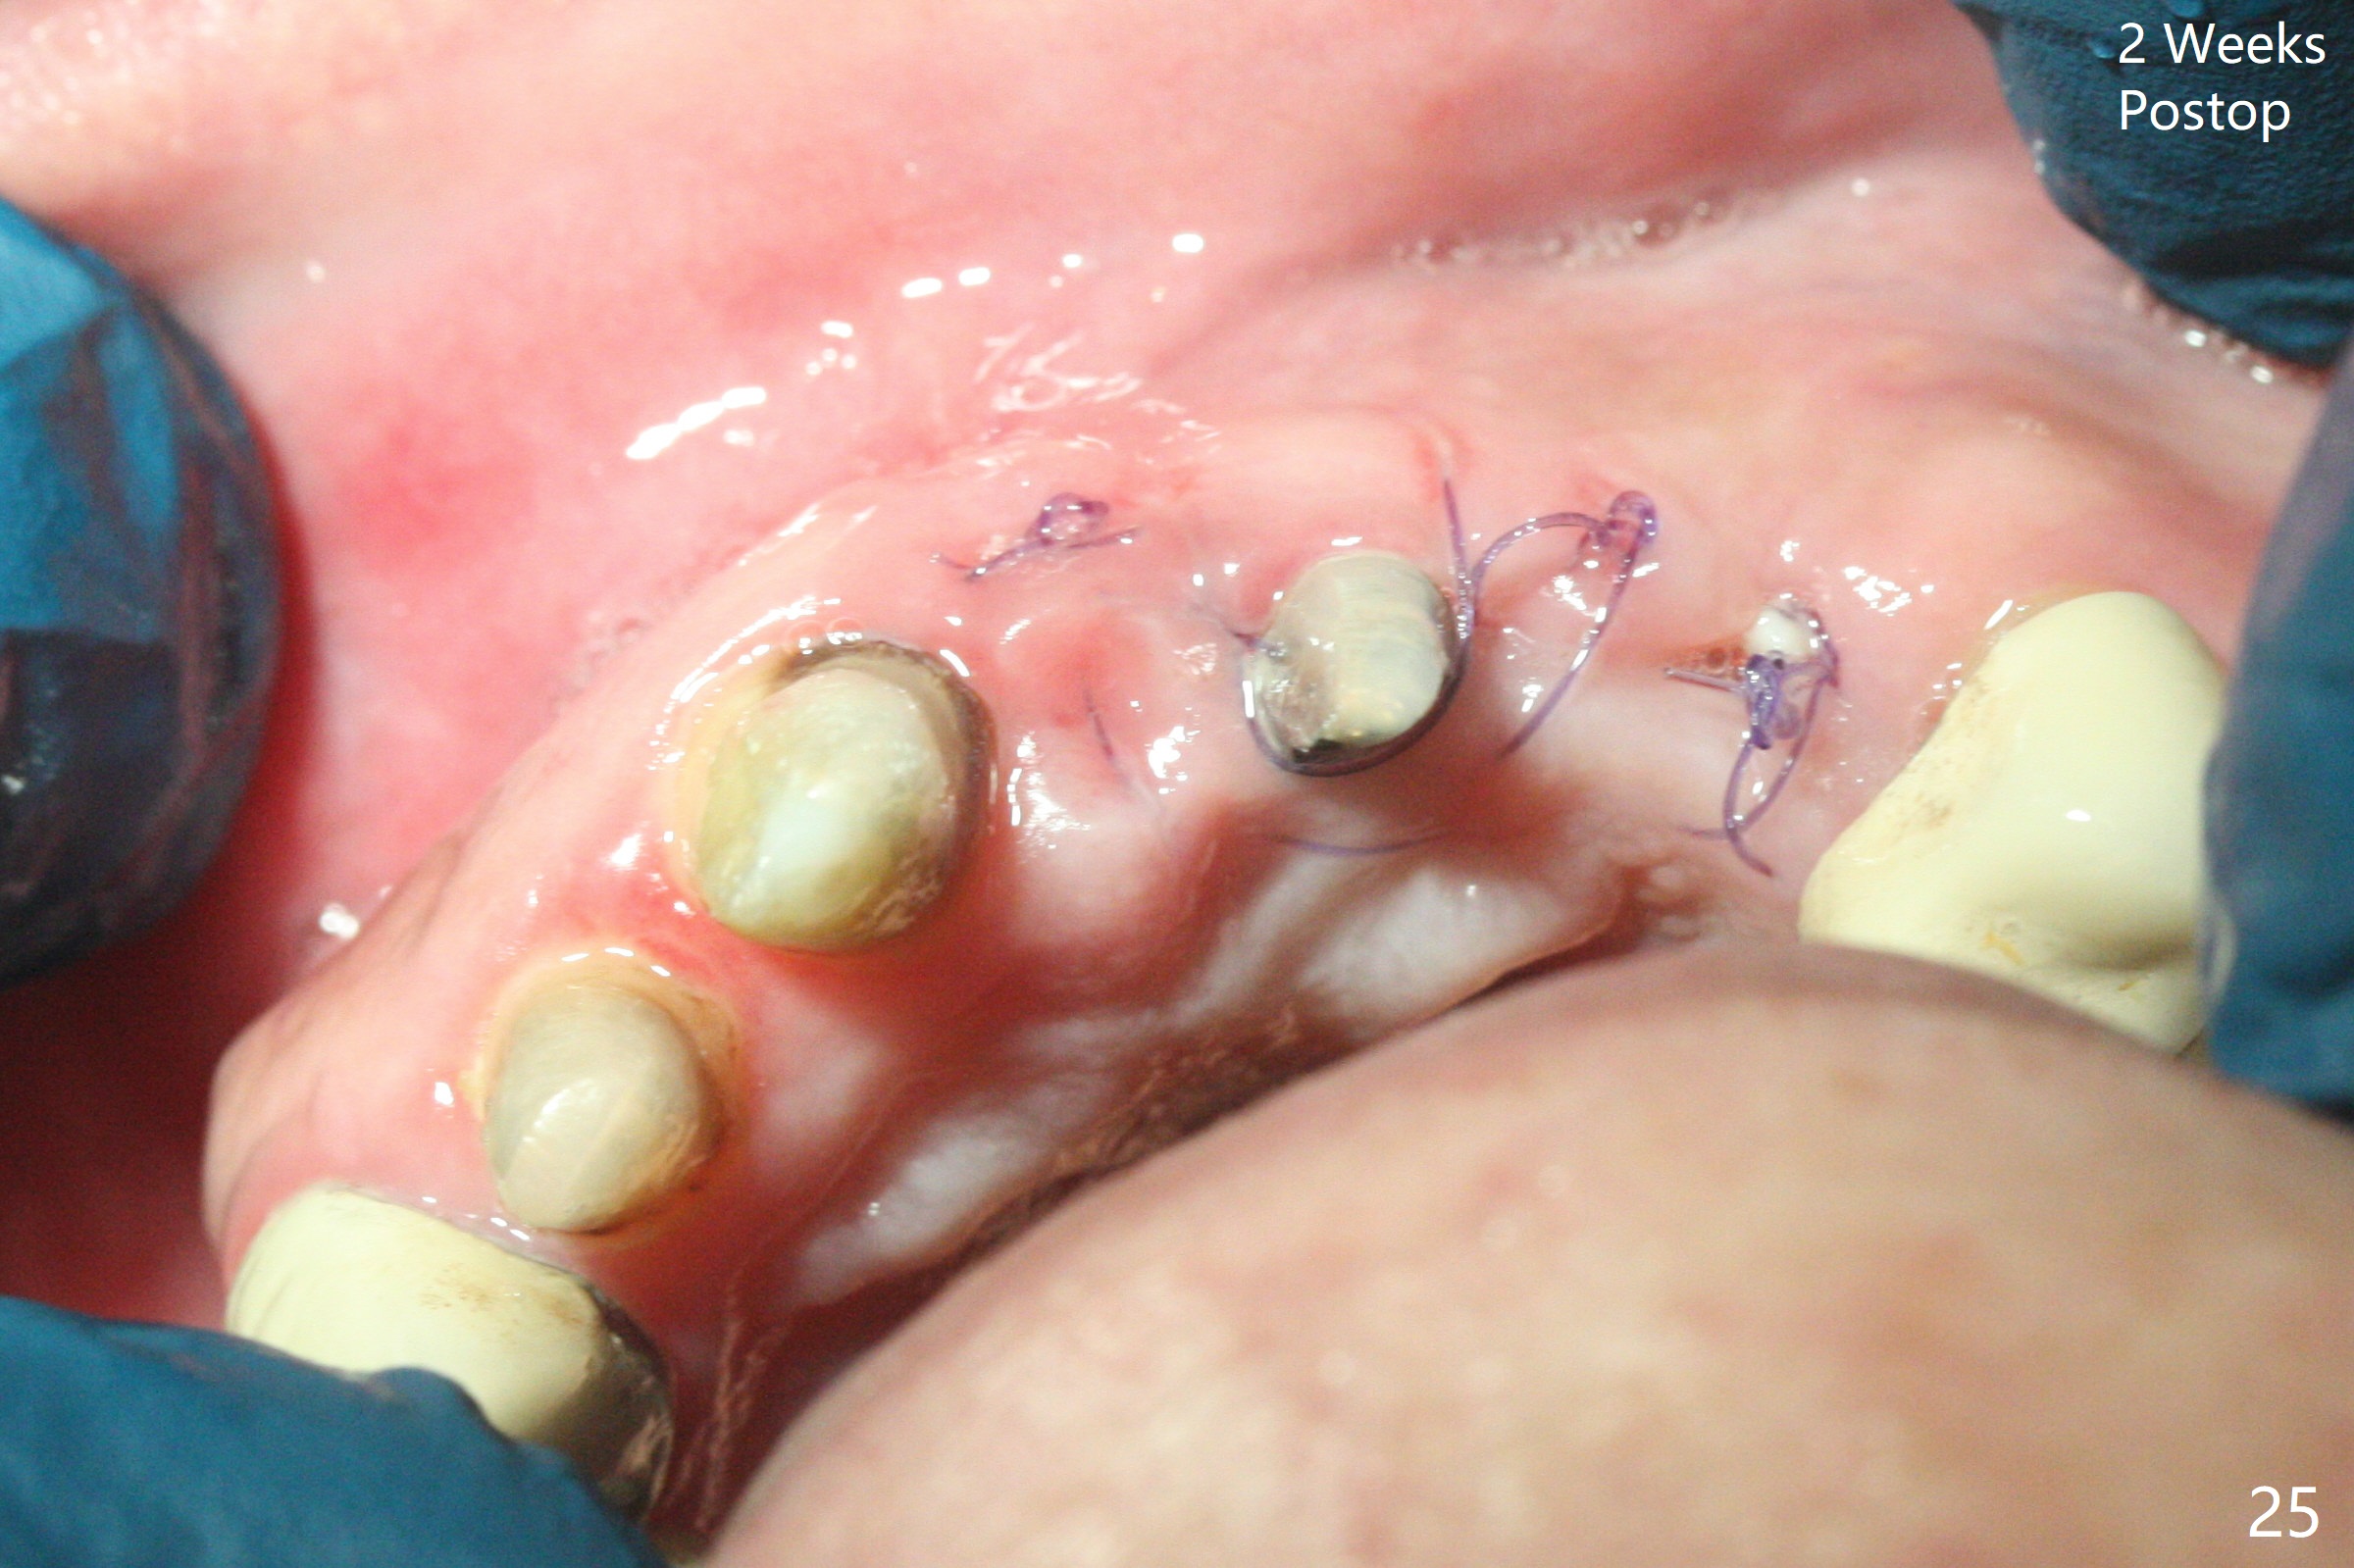

The mesiobuccal margin at #8 is redefined 4 weeks postop (Fig.14) so that the cervical end of the temporary crown is able to move mesially (Fig.13). The most coronal portion of the bone graft at #11 begins to be detached (*). The mesial portion of the abutment at #10 will be removed (curved white line) in the following week. After removing the most coronal portion of detaching bone graft at #11, acrylic is added to form a concave pontic (Fig.15 ^). With removal of the mesial portion of the abutment at #10, the retainer is moved distal (>). Pontics form at UL1 and 3 two months postop (Fig.16 *), while there is buccal atrophy at UL1,2 (Fig.17). 术后3个月植牙区牙龈形态良好(图十八),即将暴露,放置愈合基台。图十九是在右上1根管治疗时(基台放置后五天)拍摄。左上3术后3个月3个星期,1,2唇侧塌陷(图二十)。叶状植体处牙槽嵴往根尖萎缩(图二十一:^)。尽管做了松弛切口,放入事先预备的粘性骨粉后,几乎没有空间放置结缔组织移植物,恰好还没有取。放置PRF膜后,使用4-0 Monoglyc缝线缝合。牙龈似乎冠方移位(图二十二:箭头)。植骨后,唇侧仿佛饱满多了(图二十三:*)。骨粉放置于左上1,2唇侧和牙槽嵴(图二十四:*,与之前(图十九)对比)。后者有助于牙龈冠方移位,而前者有助于增加唇侧饱满度。植骨术后两周唇侧仍饱满(图二十五,六)。植骨后四个月牙冠粘固,两个月后,病人抱怨10号牙左右食物坎塞(图二十七),9/10牙冠撤除,10基台边缘加深,重做临时牙冠,同时增加9凹陷(pontic)。一个月后,9/10临时牙冠修整两次,11永久性牙冠撤除,也制备临时牙冠,外形明显改善(图二十八)。